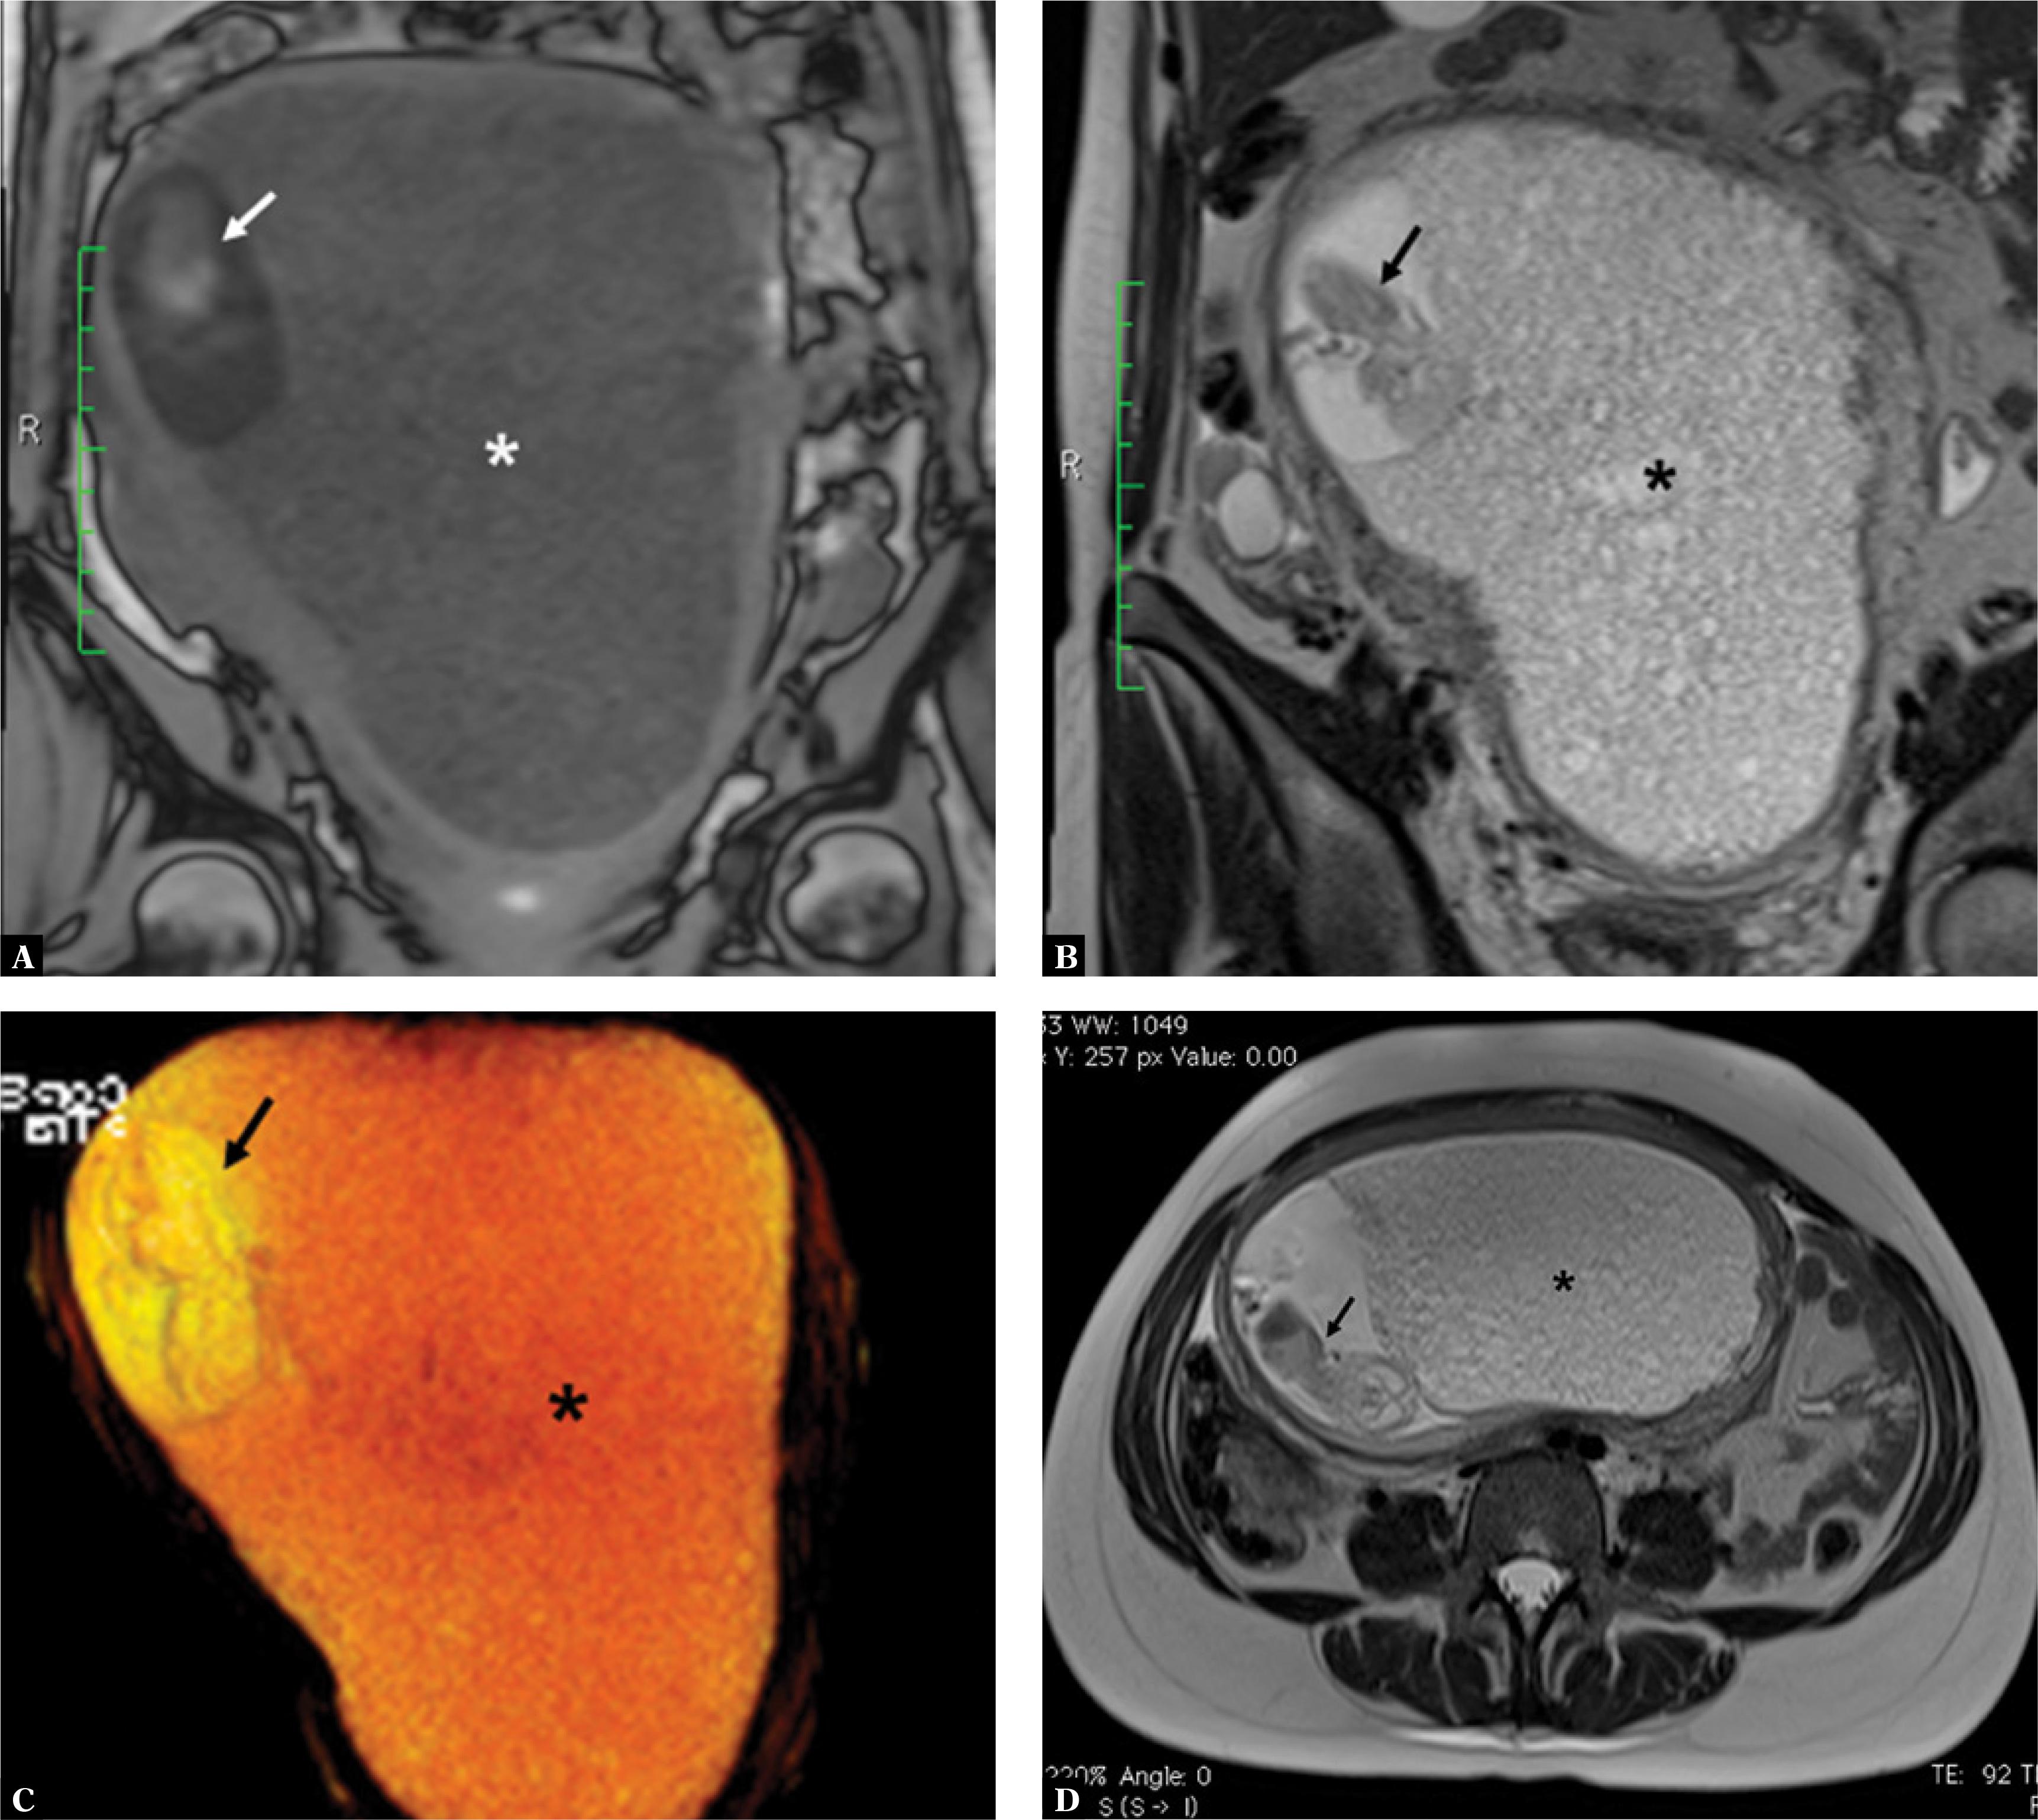

A three-dimensional (3D) ultrasound in HDlive rendering mode showed a realistic image of a fetus coexisting with a hydatidiform mole (Fig. 2). Magnetic resonance imaging (MRI) was performed to better determine the relationship between the living fetus and the hydatidiform mole. T1- and T2-weighted MRI images showed an enlarged uterus filled with amorphous heterogeneous material coexisting with a live fetus (Fig. 3), along with a distinct junction between the myometrium and the molar tissue but without evidence of myometrial invasion. These findings were compatible with the diagnosis of a twin pregnancy with a complete hydatidiform mole and a coexisting live fetus.

Fig. 3

A. Magnetic resonance imaging (MRI; coronal T1-weighted image) shows placental molar degeneration (*) and the fetus (arrow). B. MRI (coronal T2-weighted image) shows placental molar degeneration (*) and the fetus (arrow). C. Three-dimensional (3D) reconstruction from a T2-weighted true FISP sequence (coronal view) showing placental molar degeneration (*) and the fetus (arrow). D. An MRI (axial T2-weighted image) scan shows placental molar degeneration (*) and the fetus (arrow)